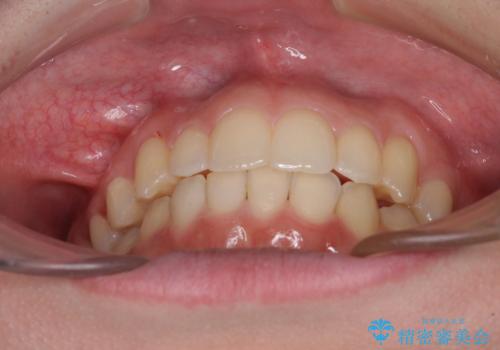

骨格的に左右にずれいている 前歯のデコボコをインビザラインで解消

- 前歯のデコボコと八重歯を気にして来院された患者様です。

叢生の程度は中等度であったため、IPR(歯と歯の間を削る)と歯列の側方拡大をメインに、インビザラインを用いて歯列を改善することとしました。

また、下顎骨の右側変位による右側臼歯の咬合を改善させるよう試みることとしました。

右側の咬合改善を目標に様々な手法を用いましたが、骨格的なズレによる不正咬合はインビザラインでは改善することができませんでした。